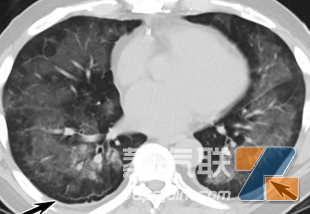

通过附上小王的肺部CT图片(如图1所示),我们可以清晰地看到他的肺部存在明显的炎症和肺气肿。这些病变使得小王的肺部功能逐渐丧失,严重影响了他的生活质量。